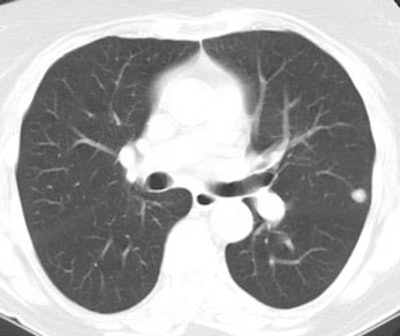

True negative PET scan: The patient in the scan below had a 1.5 cm left upper lobe nodule (shown below) that could be retrospectively identified on a prior CT scan at which time it measured only 4 mm. A PET scan was performed (below right), but demonstrated no uptake in the lesion (some cardiac activity can be seen more anteriorly). Because the nodule had enlarged from a prior exam, the nodule was resected and found to be a granuloma. Nodules larger than 1.5 cm that are negative on PET scans have a highly likelihood for representing benign or indolent lesions. |